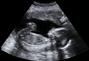

مع حلول الشهر السادس،يبدأ الجنين بالتطور،ليصل إلى حاله شبه مكتملة،أما أهم التغيرات التي ستطرأ على جنينك فهي كالتالي:في نهاية الشهر السادس يصبح طول الجنين حوالي32 سم ووزنه حوالي 750 جم.فى الشهر السادس يكون جلد الجنين رقيقاً ولامعاً.تكون بصمات الأصابع واضحة وتبدأ الجفون بالانفصال.من الممكن أن تحدث الولادة فى الشهر السادس , وذلك قد يتطلب عناية فائقة.يمكن أن يقوم الطفل 20 إلى 60 حركة في نصف ساعة، أما إذا كان نشيطاً فقد ينجز 110 حركات.ينام الآن لساعات طويلة ويصحو طوال ساعات أيضاً.تصبح السمات أكثر وضوحاً.تطور الرئتين ولكن ليس بالقدر الكافي إذا تم الوضع في الشهر السادس، فهما لن تكونا كاملتين قبل نهاية الشهر الثامن.